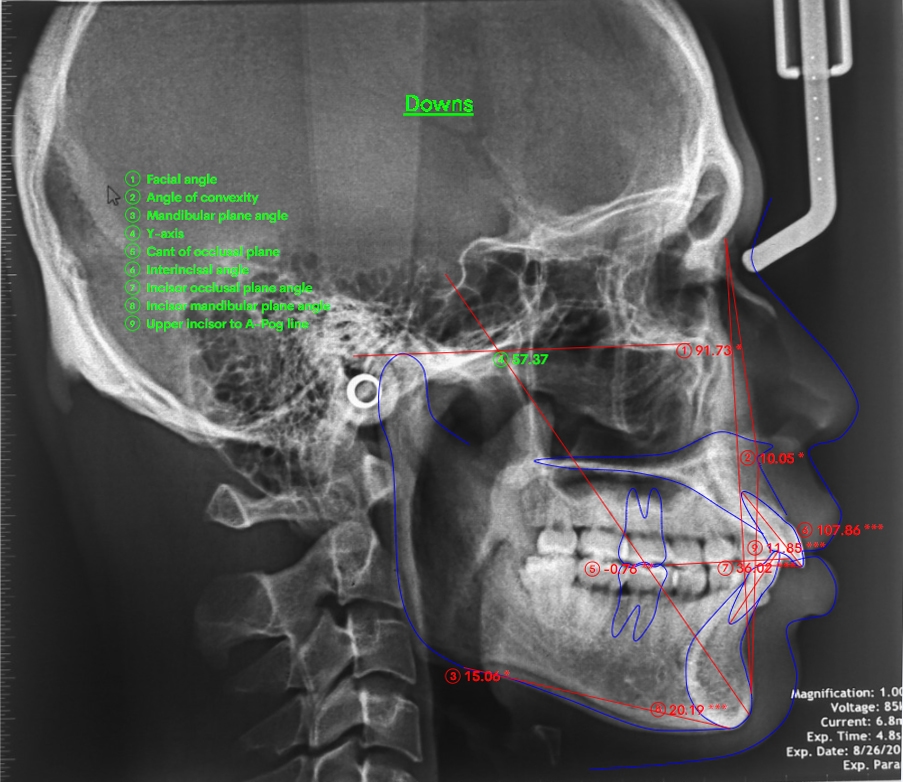

Xử lí: Muốn đóng được khoảng thì cần giải quyết vấn đề cắn sau trước, không giải quyết được cắn sâu trong case này thì sẽ không thể đóng được khoảng và càng kéo cố đóng khoảng thì càng bị hiệu ứng cuộn răng hơn. Tiến hành gắn mắc cài 2 ống, bẻ cung UA TMA 17×25 san bằng lại mặt phẳng cắn. Chuyển lại dây, căn thẳng đường giữa và đóng kín khoảng. Duy trì và tháo niềng chia tay gymer boy

Kết quả: khuôn mặt hô được giải quyết, khớp cắn hai hàm được xử lí về bình thường, tạo ổn định kết quả lâu dài.